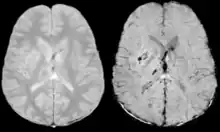

Stroke and hemorrhage

Diffusion weighted imaging offers a powerful means to detect acute stroke. Although it is well known that gradient echo imaging can detect hemorrhage, it is best detected with SWI. In the example shown here, the gradient echo image shows the region of likely cytotoxic edema whereas the SW image shows the likely localization of the stroke and the vascular territory affected (data acquired at 1.5 T).

The bright region in the gradient echo weighted image shows the area affected in this acute stroke example. The arrows in the SWI image may show the tissue at risk that has been affected by the stroke (A, B, C) and the location of the stroke itself (D). The reason that we are able to see the affected vascular territory could be because there is a reduced level of oxygen saturation in this tissue, suggesting that the flow to this region of the brain could be reduced post stroke. Another possible explanation is that there is an increase in local venous blood volume. In either case, this image suggests that the tissue associated with this vascular territory could be tissue at risk. Future stroke research will involve comparisons of perfusion weighted imaging and SWI to learn more about local flow and oxygen saturation.